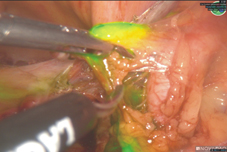

本院所使用的淋巴造影劑為引朵花青綠(Indocyanine green, ICG)。此造影劑可在淋巴管中快速遷移至前哨淋巴結,術中使用螢光攝影機檢測即可以檢測有無淋巴結顯影(如圖二)。亞東醫院婦癌團隊分析了過去兩年半共34例接受前哨淋巴結造影的子宮內膜癌患者的治療結果,發現與國際發表結果相同;前哨淋巴造影並不會增加癌症復發比率或死亡率,反而可以減少手術流血量且摘除之淋巴結數量也較少。

圖二、前哨淋巴造影綠色螢光為顯影的淋巴結